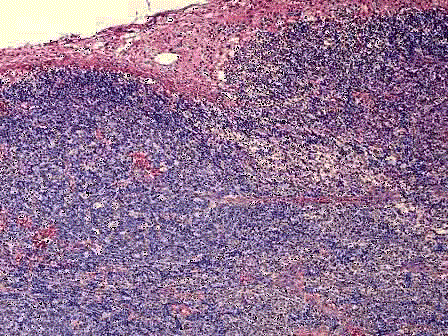

一患者颈部淋巴结肿大,直径达3cm,活检如图所示,淋巴滤泡弥漫增生,滤泡间小动脉增生、透明变性,并长入滤泡中心内;生发中心内小动脉内皮细胞肿胀,管壁内均质...

问题 一患者颈部淋巴结肿大,直径达3cm,活检如图所示,淋巴滤泡弥漫增生,滤泡间小动脉增生、透明变性,并长入滤泡中心内;生发中心内小动脉内皮细胞肿胀,管壁内均质、红染物质呈同心圆状沉积。应首先考虑何种疾病 ( )

选项 A.反应性滤泡增生 B.滤泡性淋巴瘤 C.巨大淋巴结增生症 D.套细胞淋巴瘤 E.胸腺瘤

答案 C